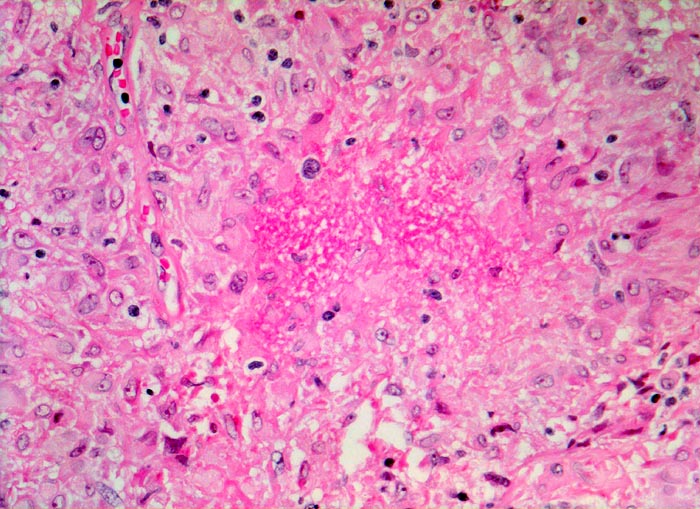

Lymphknotensarkoidose (Morbus Boeck): Granulom mit Nekrose

Exsudatives Granulom mit zentraler Nekrose (Bildmitte).

Vergrösserte inguinale Lymphknoten bei bekannter Sarkoidose mit Befall der Lungen.

Seltenerweise kann man auch bei einer Sarkoidose verkäsende Granulome nachweisen. Zum histologischen Ausschluss einer produktiven Tuberkulose muss in diesem Fall eine Ziehl-Neelsen-Färbung durchgeführt werden, wobei ein negativer Bakteriennachweis die Tuberkulose nicht ausschliesst.